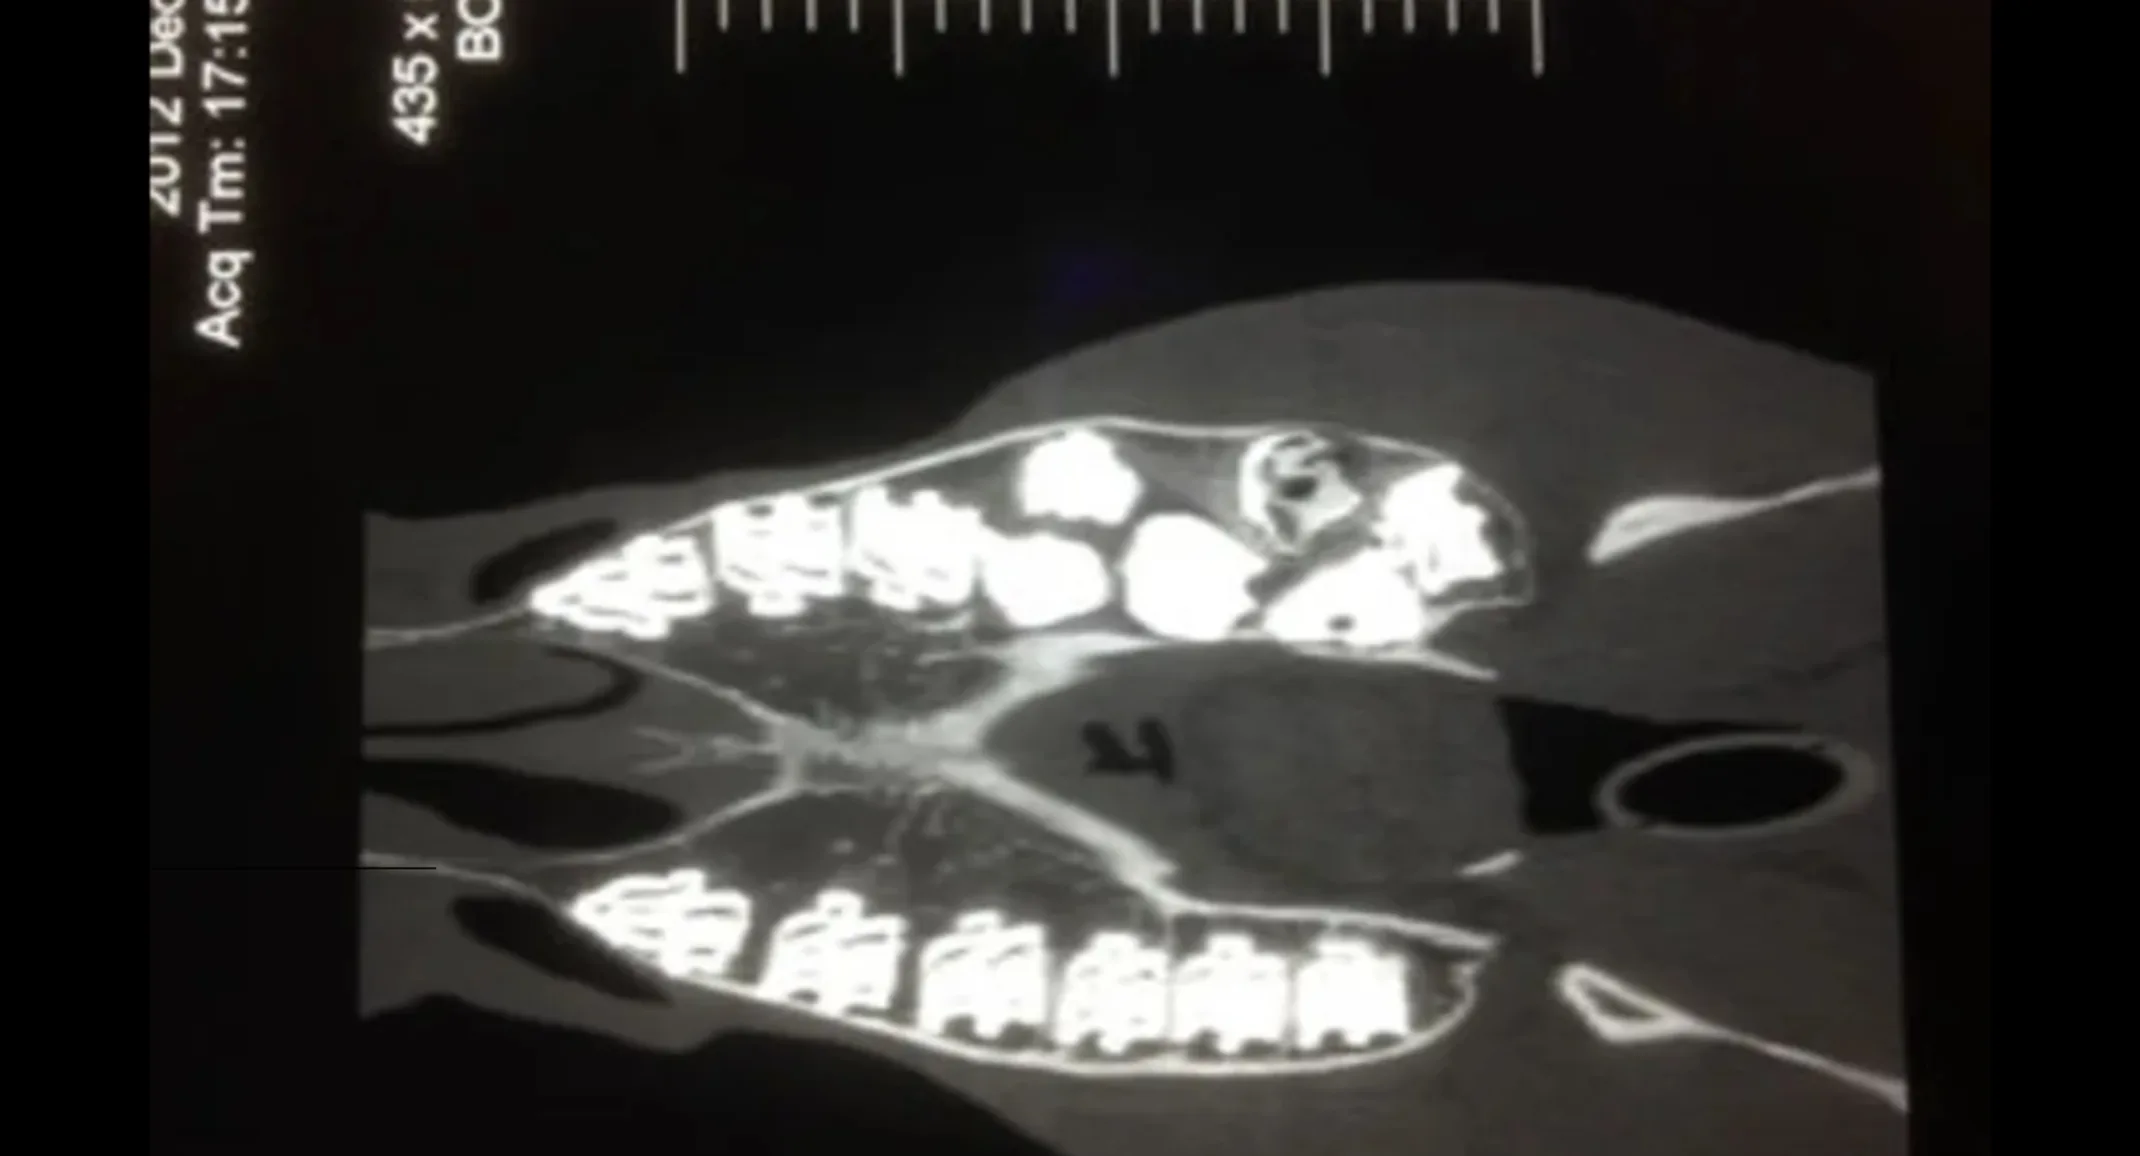

Significant dental abnormalities found during a routine dental examination. Dental radiographs identified supernumerary (extra) cheek teeth in the left maxillary arcade, one large malformed cheek tooth and one fractured cheek tooth.

Horse was sent to UC Davis for Skull CT, which identified the presence of double molars along the left maxillary arcade.